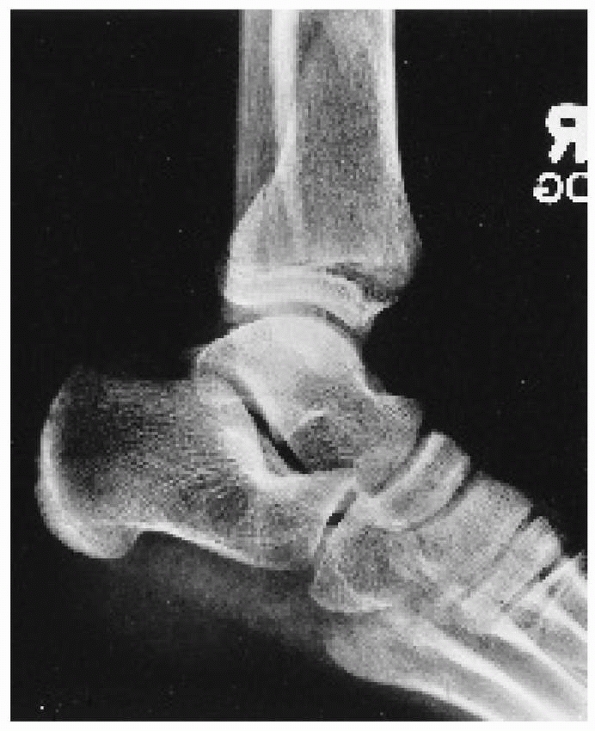

![]() |

FIGURE 26-10 A. Anteroposterior radiograph of Salter Harris type III/juvenile Tillaux Fracture. B. Lateral radiograph of Salter Harris type III/juvenile Tillaux Fracture.

|

III fracture involving the anterolateral distal tibia. The portion of

the physis not involved in the fracture is closed (Fig. 26-10).